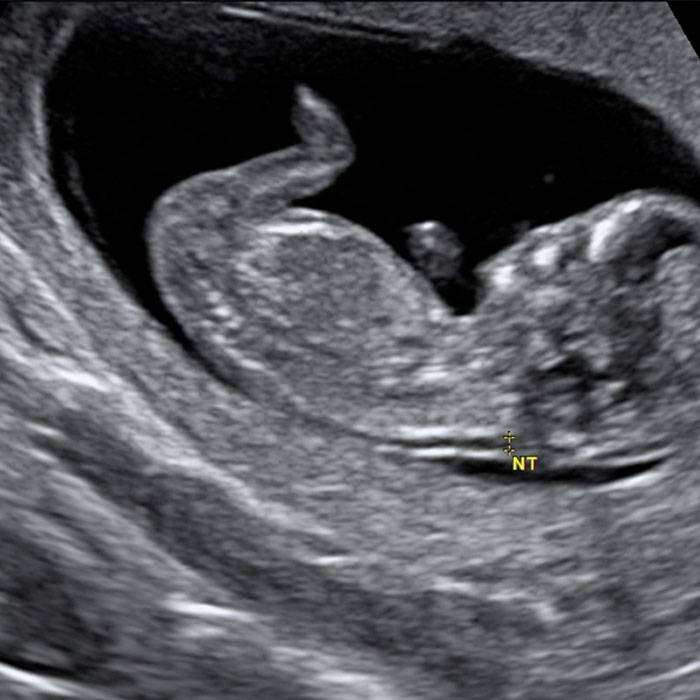

Ense Kalınlığı Ölçümü:

Doktorun bebeğin ensesinin arkasındaki alanı ölçmesine yarayan detaylı ultrason tetkikidir. Kan testi sonuçları ile birleştirildiğinde bebeğin Down Sendromu riskini hesaplamada kolaylık sağlar.